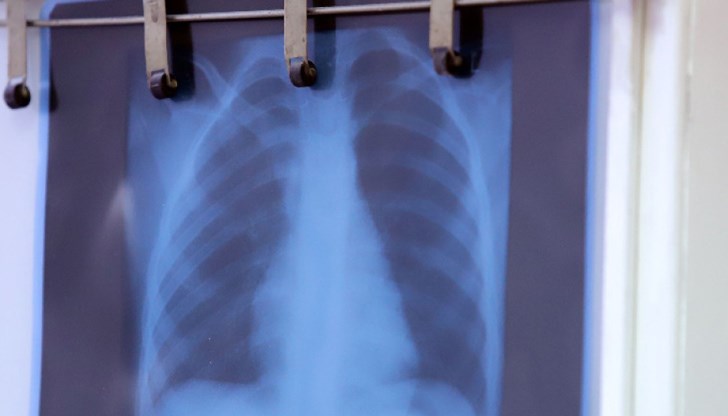

Кажете на специалиста ясно за вашите симптоми. Не се тревожете, ако не ви бъде поставена веднага диагноза, тъй като пневмонията може да бъде потвърдена само след флуорография.